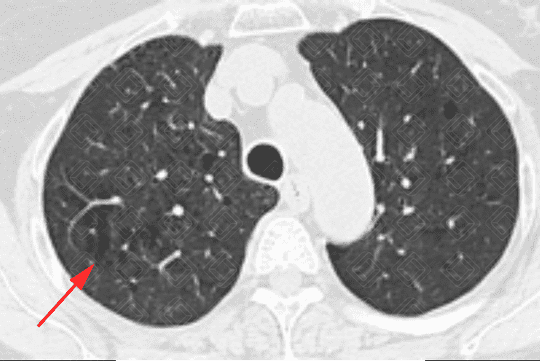

Descrição das figuras 3, 4, 5 e 6: Tomografia computadorizada do tórax seguida de aquisições coronais, sagitais e axiais mostrando as extensas áreas de enfisema centrolobular dispersas pelo parênquima pulmonar (setas vermelhas).

• Tomografia computadorizada do tórax: Este método é mais sensível e específico que a radiografia de tórax na avaliação do enfisema. Tem sido empregado para detectar, quantificar e caracterizar a doença. A tomografia é capaz de diferenciar os vários tipos de enfisema, que pode ser classificado, de acordo com a região do ácino acometida, em proximal (centrolobular ou centroacinar - figuras 3, 4, 5, 6, 9, 10 e 11 ), distal (parasseptal - figuras 7, 8, 9, 10 e 11 ) ou todo ácino (panacinar ou panlobular).